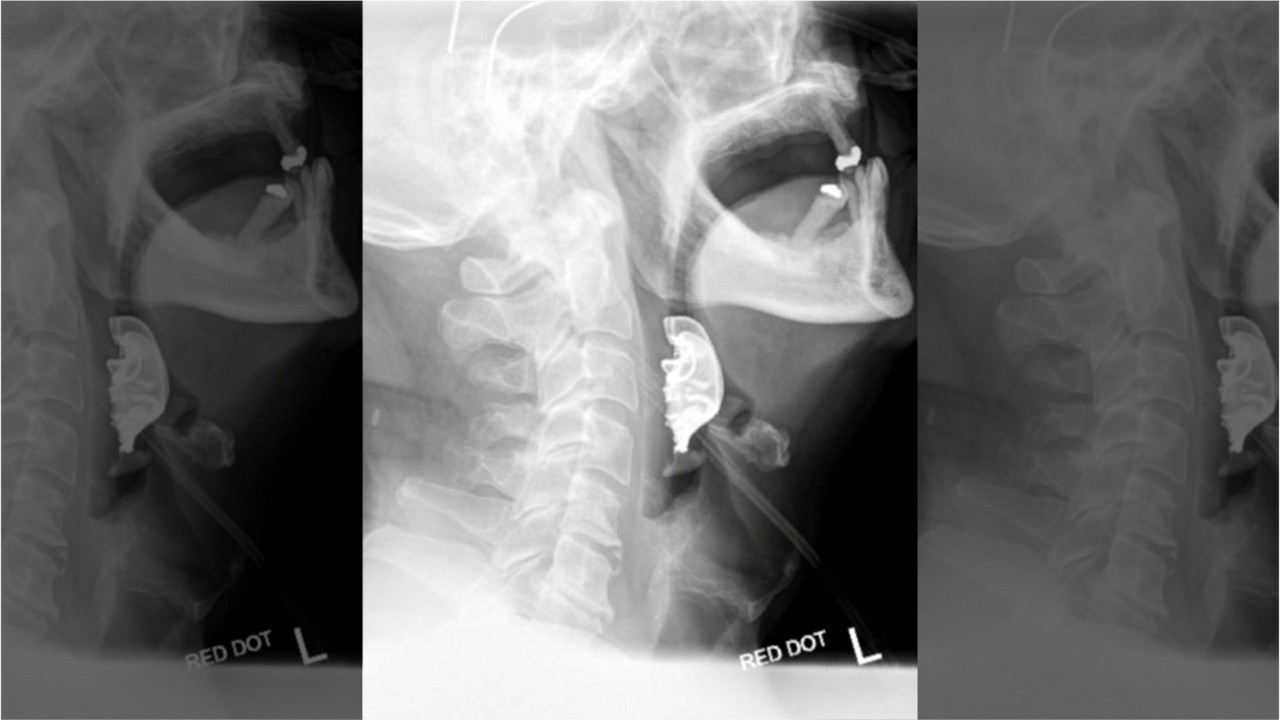

But he didn’t improve and was admitted to the hospital just two days later. Medics told doctors they “spotted a semi-circular object lying across his vocal cords,” according to SWNS.

The man reportedly thought his dentures were lost while he was in the hospital to remove the lump.